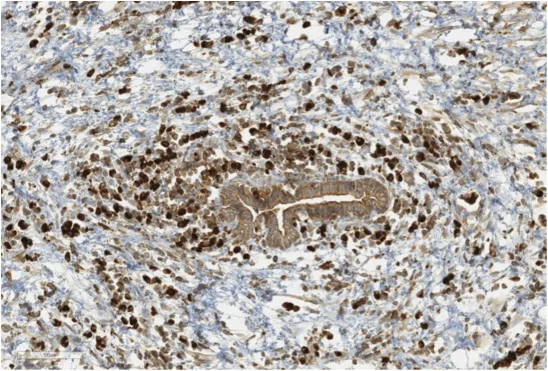

Figure 2. LPSP : Intense marquage des plasmocytes IgG4+ en position péri-canalaire

5. Abondance de plasmocytes à IgG4 (> 10 plasmocytes à IgG4 par grand champ). Cette lésion dénommée LPSP pour Lympho-Plasmocytic Sclerosing Pancreatitis est la signature de la PAI de type I (Fig. 2).